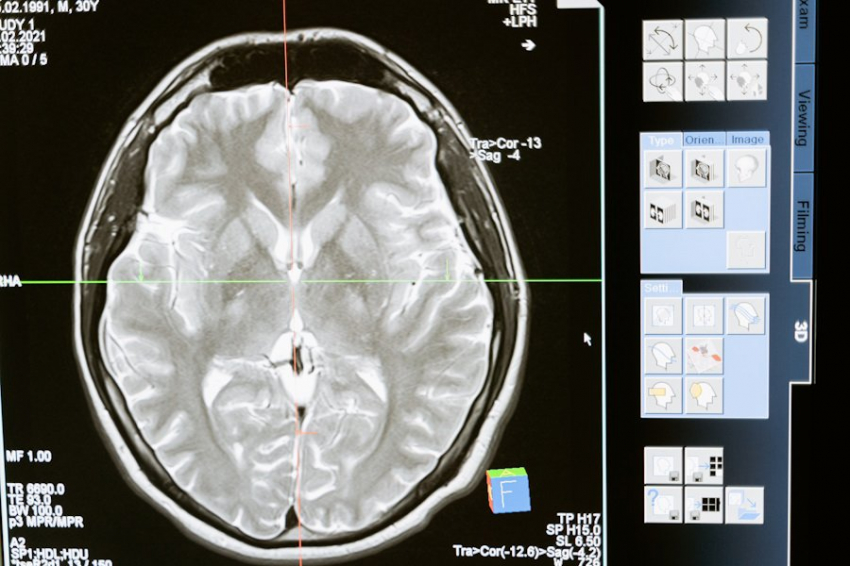

Исследование, опубликованное на портале The EMBO Journal, раскрывает новую связь между старением и нейродегенеративными заболеваниями. Учёные из Tokyo Medical and Dental University (TMDU) изучили белок PQBP3 и его роль в старении клеток.

Исследователи обнаружили, что PQBP3, находящийся в нуклеусе* клетки, перемещается в цитоплазму во время старения, что приводит к нестабильности ядерной мембраны и утечке ДНК. Этот процесс связан с ухудшением состояния клеток и может быть ключом к лечению таких заболеваний, как болезнь Альцгеймера и болезнь Паркинсона.

Учёные подчёркивают, что потеря функции PQBP3 может быть как причиной нейродегенерации, так и фактором риска рака. Эти результаты открывают перспективы для разработки новых терапий, направленных на улучшение состояния мозга и клеток в целом.